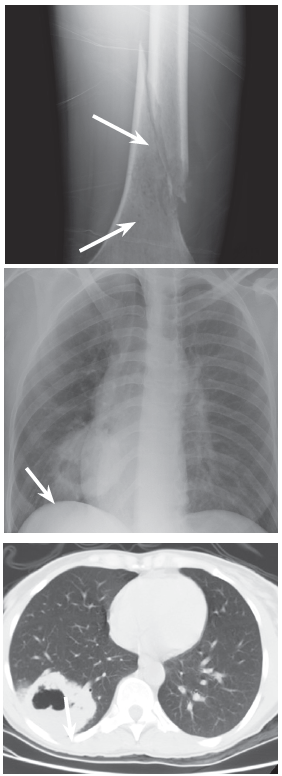

Laboratory testing. A radiograph of the femur showed an aggressive mottled lesion in the distal diaphysis with a pathologic fracture. A chest radiograph revealed a 6-cm round mass in the right lower lung with central lucency, clearly defined by a chest CTscan as a thick-walled cavitary mass.

Results of a GI panel; calcium, phosphorus, alkaline phosphatase, and alpha-fetoprotein levels; and serum protein electrophoresis (SPEP), urine protein electrophoresis (UPEP), and urinalysis results were normal. Acid-fast bacillus and fungal sputum cultures were negative. White blood cell count was 12,000/µL, and erythrocyte sedimentation rate (ESR) was 42 mm/h. A bone scan showed increased uptake in the distal femur only. CT scans of the brain, abdomen, and pelvis were negative.

The patient’s thigh was splint, and she was admitted to the hospital. She then underwent repair of the fracture; intra-operative femur tissue biopsy showed metastatic poorly differentiated non-small cell carcinoma. Immunoperoxidase staining suggested primary lung adenocarcinoma. The patient received 800-centigray radiation palliative therapy to the left femur and was scheduled for outpatient palliative chemotherapy.

Discussion. A pathologic fracture occurs in abnormal bone, typically with normal activity or minimal trauma.1 Common causes are osteoporosis, osteomalacia, Paget disease, osteopetrosis, osteogenesis imperfecta, fibrous dysplasia, primary benign tumor, primary malignant tumor, and metastatic tumor. Relevant history includes degree of trauma, constitutional symptoms, previous history of malignancy, smoking, dietary habits, and exposures. A stool guaiac test and palpation for lymphadenopathy, thyroid nodules, breast masses, prostate nodules, and rectal masses are warranted.

Radiographs should be carefully assessed for osteopenia, periostal thickening, abnormal radiodensities, and calcifications of small vessels. Malignant and metastatic lesions are usually eccentric and involve the cortex. New bone formation suggests osteosarcoma; calcifications are seen in chondrosarcomas; and periostal thickening is less likely to be malignant. If a suspected metastatic lesion is found, a full skeletal survey should be done; common sites of bone metastasis include the spine, ribs, pelvis, femur, and humerus. If a bone scan shows uptake at 5 or more sites, metastatic malignancy is almost certain. Commonly indicated laboratory studies include a complete blood cell count, urinalysis, SPEP, UPEP, liver function tests, and measurement of alkaline phosphatase, calcium, phosphorus, ESR, and prostate-specific antigen in males.